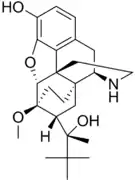

The pharmacodynamic response to an opioid depends upon the receptor to which it binds, its affinity for that receptor, and whether the opioid is an agonist or an antagonist. For example, the supraspinal analgesic properties of the opioid agonist morphine are mediated by activation of the μ1 receptor; respiratory depression and physical dependence by the μ2 receptor; and sedation and spinal analgesia by the κ receptor. Each group of opioid receptors elicits a distinct set of neurological responses, with the receptor subtypes (such as μ1 and μ2 for example) providing even more [measurably] specific responses. Unique to each opioid is its distinct binding affinity to the various classes of opioid receptors (e.g. the μ, κ, and δ opioid receptors are activated at different magnitudes according to the specific receptor binding affinities of the opioid). For example, the opiate alkaloid morphine exhibits high-affinity binding to the μ-opioid receptor, while ketazocine exhibits high affinity to ĸ receptors. It is this combinatorial mechanism that allows for such a wide class of opioids and molecular designs to exist, each with its own unique effect profile. Their individual molecular structure is also responsible for their different duration of action, whereby metabolic breakdown (such as N-dealkylation) is responsible for opioid metabolism.

Several semi-synthetic opioids were developed in Germany in the 1910s. The first, oxymorphone, was synthesized from thebaine, an opioid alkaloid in opium poppies, in 1914.[228] Next, Martin Freund and Edmund Speyer developed oxycodone, also from thebaine, at the University of Frankfurt in 1916.[229] In 1920, hydrocodone was prepared by Carl Mannich and Helene Löwenheim, deriving it from codeine. In 1924, hydromorphone was synthesized by adding hydrogen to morphine. Etorphine was synthesized in 1960, from the oripavine in opium poppy straw. Buprenorphine was discovered in 1972.[228]